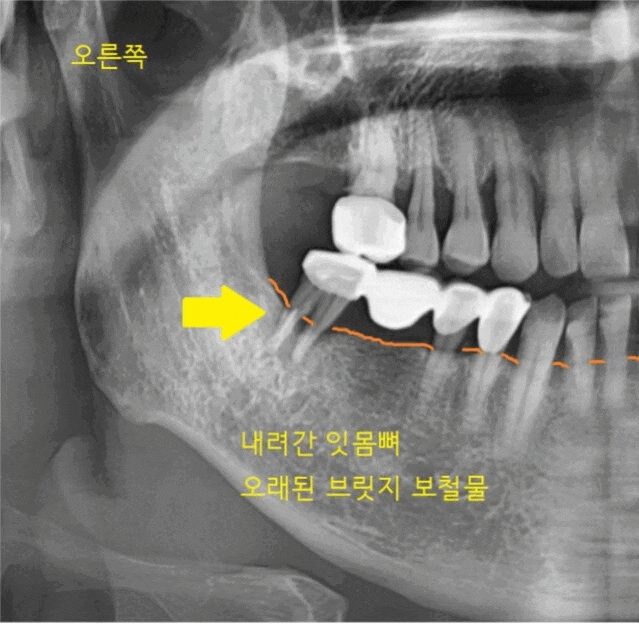

사진 속 화살표 치아를 주목해 주세요.

브릿지 치료가 되어있네요.

정상적인 잇몸뼈는 치아머리 부위까지

채워져 있어야 합니다.

잇몸뼈가 많이 내려가서

치아를 붙잡고 있는 게 없다 보니

흔들흔들했는데요.